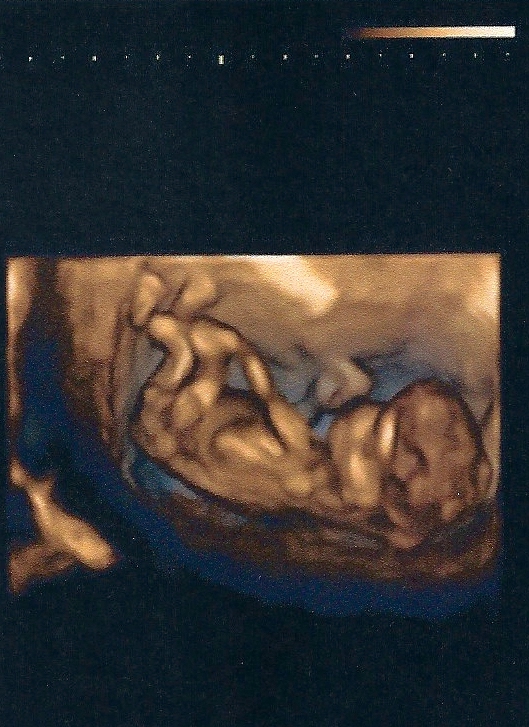

New around here and found this forum in the research of nubs... well I am stuck I can not work out what baby number 5 is... I have no feeling either way... I am sorry I dont have a good 2D shot only this one...

Thank you in advance anyone that takes the time to have a guess... this ultrasound was done at 12 weeksAttachment 7047